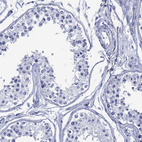

Immunohistochemistry analysis in human parathyroid gland and cerebral cortex tissues using HPA071236 antibody. Corresponding DPP4 RNA-seq data are presented for the same tissues.